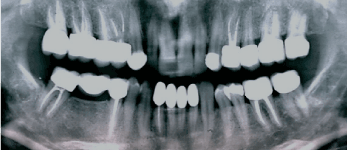

The diagnostic protocol included; auscultation for joint sounds, diagnostic local anesthesia to determine whether the pain was dental or non-dental, and antibiotic regimen to evaluate possible dental infection. None of these tests were diagnostic, according the TMJ specialist. In addition, the TMJ tomography did not reveal any pathologic condition of the condyle, the articular eminence, or any dislocation in an open or closed jaw positions (Figures 2 & 3). The symptoms were alleviated completely after a new occlusal splint with an increased thickness was fabricated and worn by the patient for 48 hours

Figure 3. Right and left TMJ tomography.